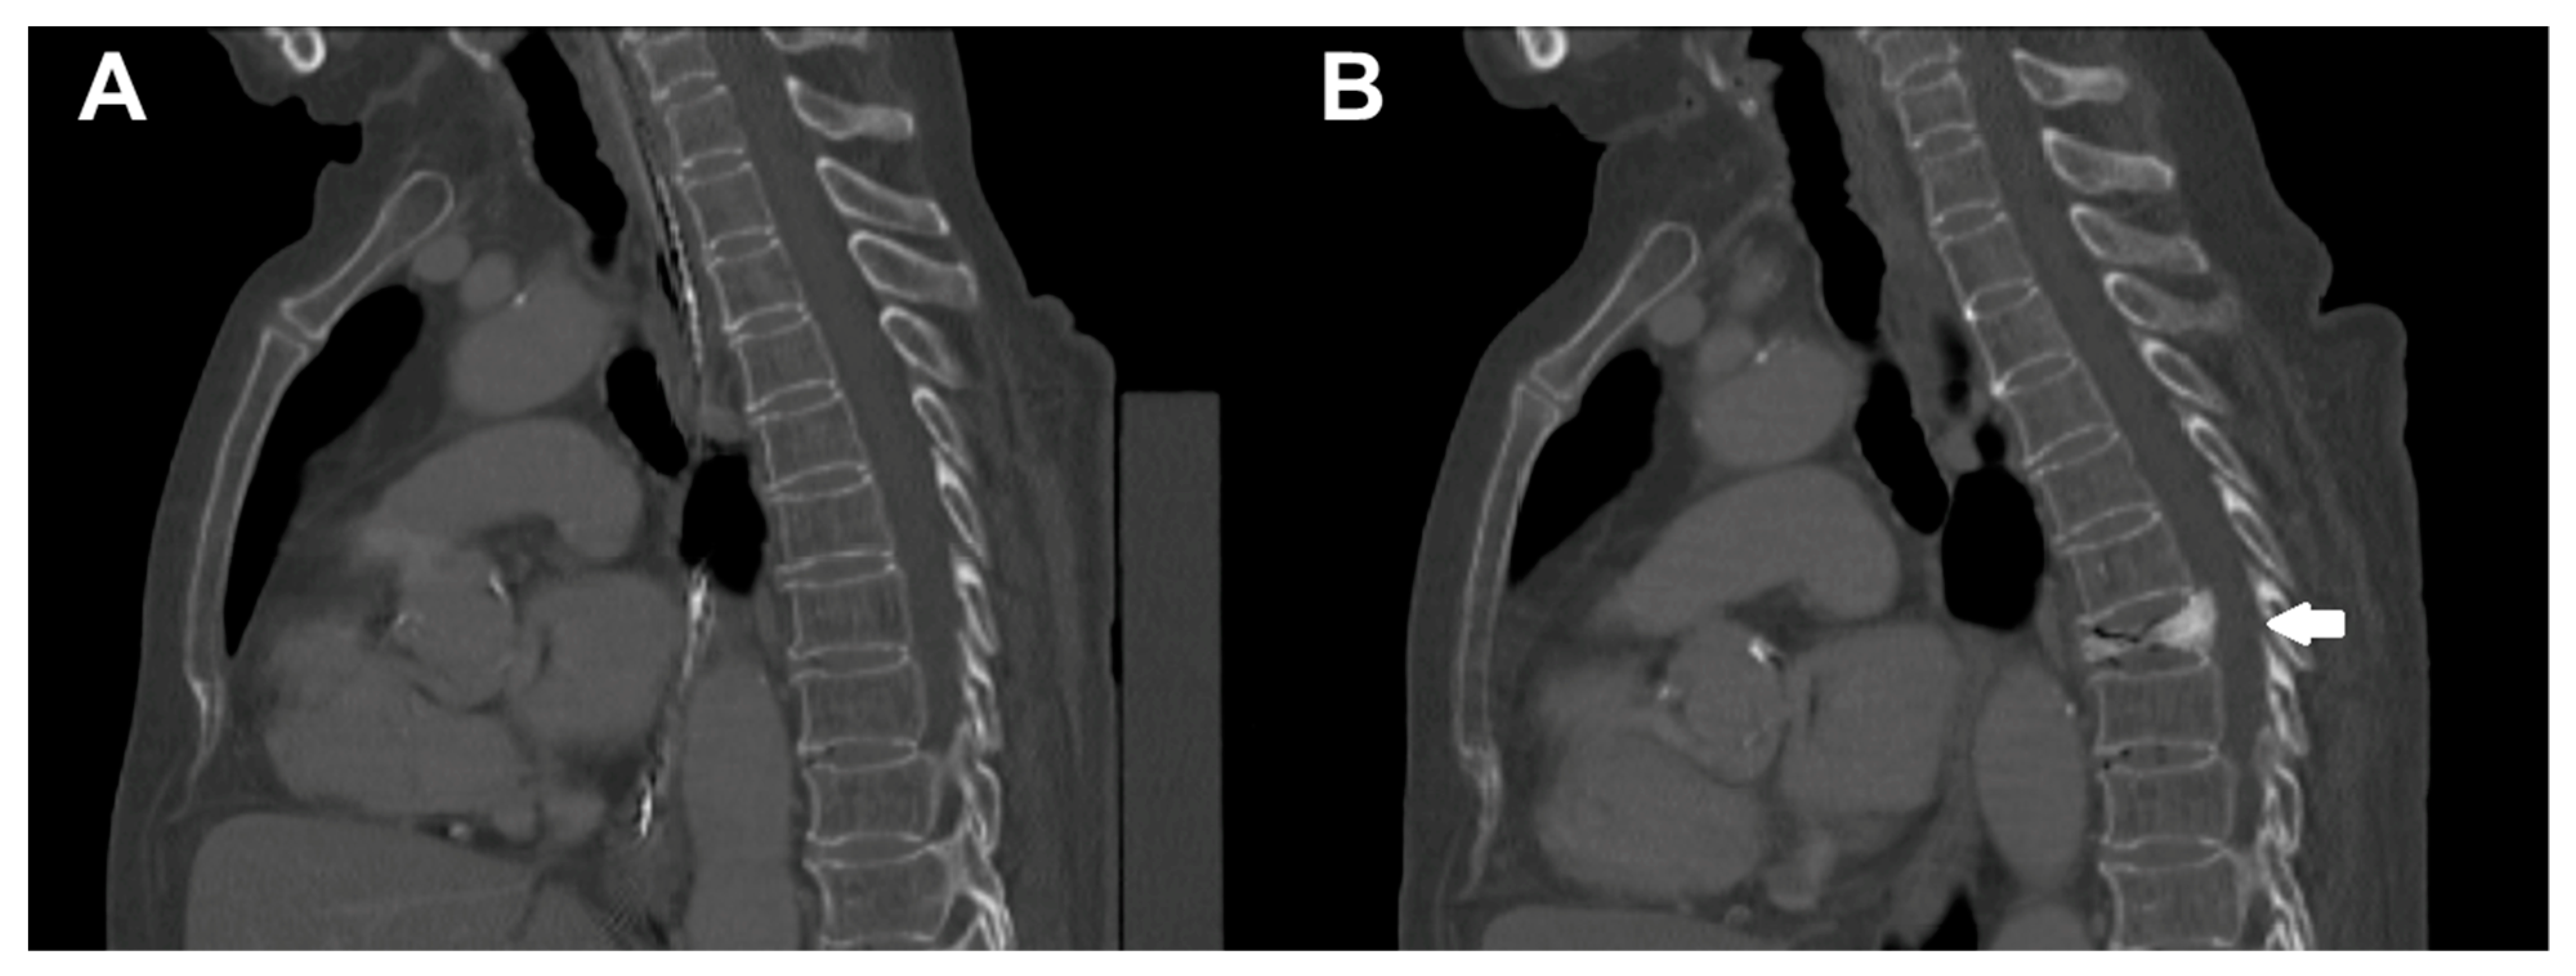

- Yeung, L.Y.; Rayudu, N.M.; Löffler, M.; Sekuboyina, A.; Burian, E.; Sollmann, N.; Dieckmeyer, M.; Greve, T.; Kirschke, J.S.; Subburaj, K.; et al. Prediction of Incidental Osteoporotic Fractures at Vertebral-Specific Level Using 3D Non-Linear Finite Element Parameters Derived from Routine Abdominal MDCT. Diagnostics 2021, 11, 208. [Google Scholar] [CrossRef]

- Baum, T.; Muller, D.; Dobritz, M.; Wolf, P.; Rummeny, E.J.; Link, T.M.; Bauer, J.S. Converted lumbar BMD values derived from sagittal reformations of contrast-enhanced MDCT predict incidental osteoporotic vertebral fractures. Calcif. Tissue Int. 2012, 90, 481–487. [Google Scholar] [CrossRef] [PubMed]